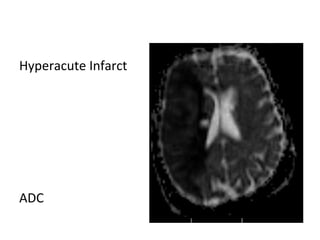

a) Hyperacute Infarct (0-6 hours)

-Diffusion is the most sensitive modality , DWI

hyperintensity & ADC map hypointensity reflect

reduced diffusivity which can be seen within minutes

of the ictus

-FLAIR may be normal , subtle hyperintensity may be

seen on FLAIR

Hyperacute Infarct

T1

T2

Flair

DWI

ADC